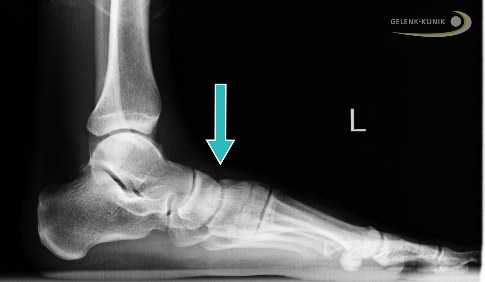

Der Knick-Senkfuß ist eine der häufigsten Fußfehlstellungen. Er äußert sich durch ein Absinken des Fußlängsgewölbes. Das Fersenbein ist meist nach außen gestellt, wodurch der Innenknöchel überlastet wird und es zu Beschwerden beim Laufen kommt. Zusätzlich ist beim Knick-Senkfuß die Zehenstellung verändert: Die Zehen zeigen nicht nach vorne, sondern beim Gehen eher nach außen. Der Arzt spricht vom Too-many-Toes-Sign.

Verschiebungsoperation des Fersenbeins

Die knöcherne Verschiebung des Fersenbeins (Mediale Displacement Osteotomy, MDO) ist geeignet, die Fehlstellung des Rückfußes auszugleichen und korrigiert vor allem die Knickfuß-Komponente. Durch die Verlagerung des Fersenbeins nach innen verändert sich auch die Zugrichtung der kräftigen Achillessehne. Dies richtet den Fuß insgesamt auf.

Die Fehlstellung des Fersenbeins verändert die Zugwirkung der starken Achillessehne: Sie wird beim Gehen nicht ausreichend gedehnt und verkürzt sich daraufhin. Diese Verkürzung spielt eine wichtige Rolle beim Aufrechterhalten der Knick-Senkfußfehlstellung. Eine Normalisierung der Fersenstellung verhindert die fortschreitende Verkürzung der Achillessehne.